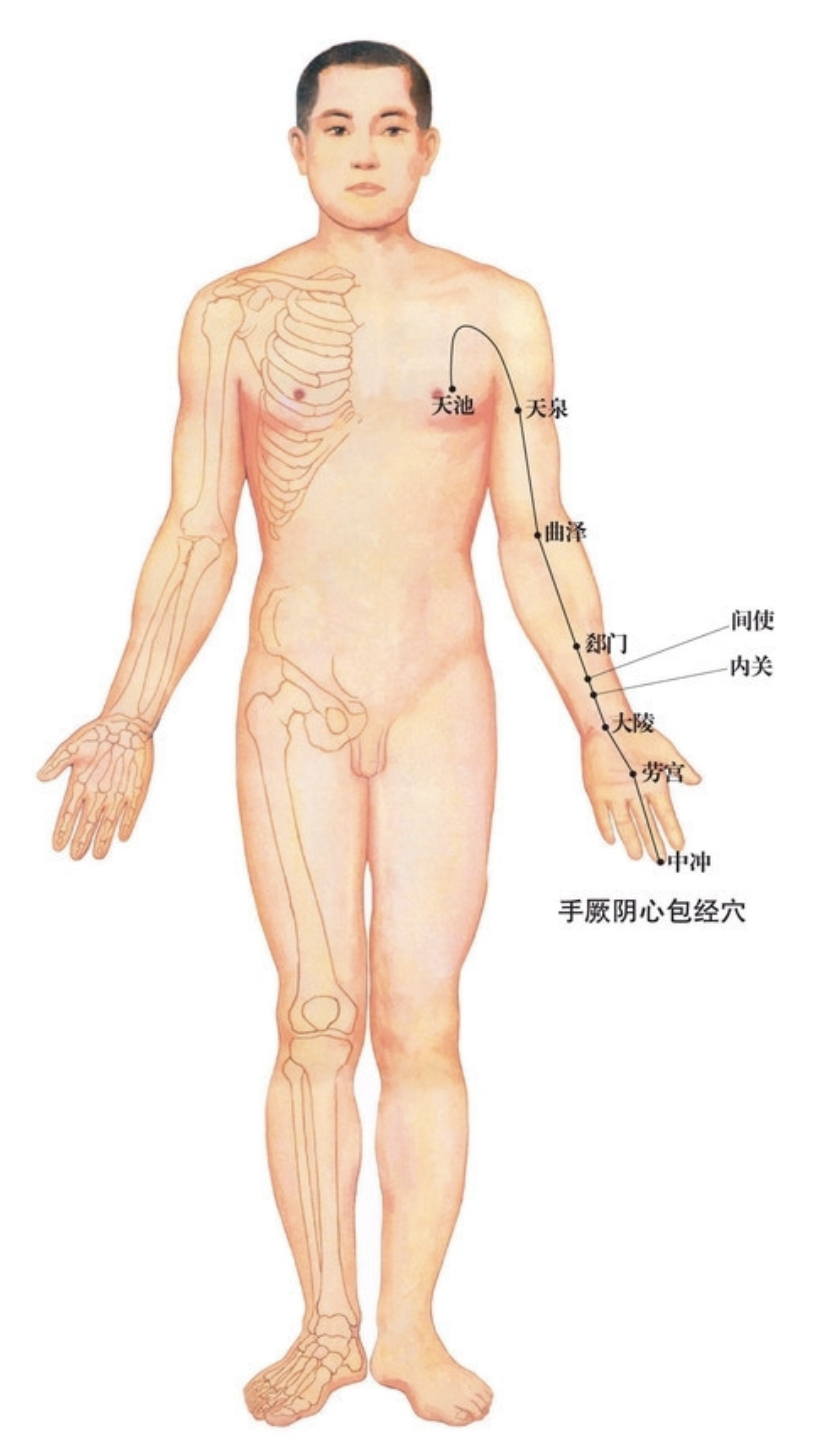

【(九)手厥阴心包经(图 10-27-1)】

2、歌诀 九穴心包手厥阴,天池天泉曲泽深,郄(xì)门间使内关对,大陵劳宫中冲侵。

3、经脉循行 起于胸中,出属心包络,向下通膈,从胸至腹依次联络上、中、下三焦。

胸部支脉:沿胸中,出于胁肋至腋下(天池),上行至腋窝中,沿上臂内侧行于手太阴和手少阴经之间,经肘窝下行于前臂中间进入掌中,沿中指到指端(中冲)。

掌中支脉:从劳宫分出,沿无名指到指端(关冲),与手少阳三焦经相接。

4、主要病候 心痛、胸闷、心惊、心烦、癫狂、腋肿、肘臂挛痛、掌心发热等。

5、主治概要 主治心、胸、胃、神志病及经脉循行部位的其他病证。